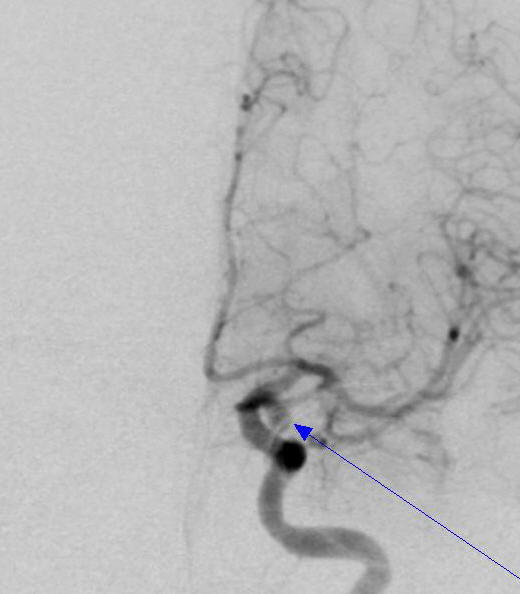

病例3